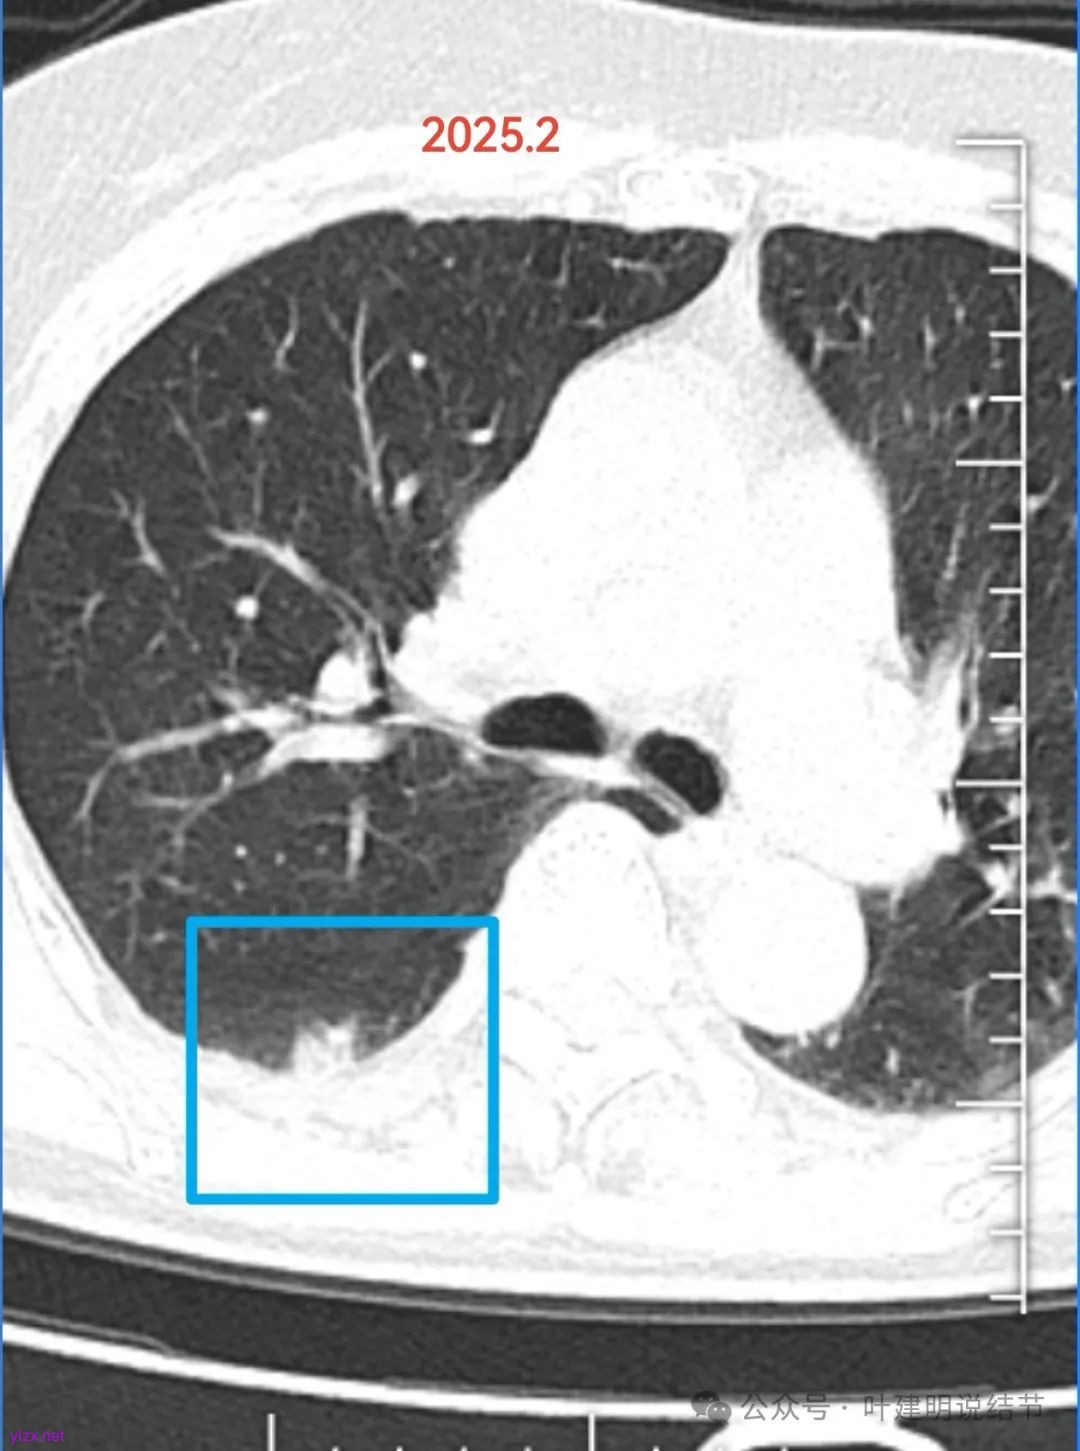

右下背段偏实性结节,整体轮廓较清,瘤肺边界欠清晰,紧贴胸膜但无明显牵拉,整体显得缺乏收缩力,边缘也说不上膨胀性。

似乎灶内有部分吸收,因为变成了类似蜂窝状了。病灶一侧贴叶间裂,一贴胸壁,均无牵拉影响。